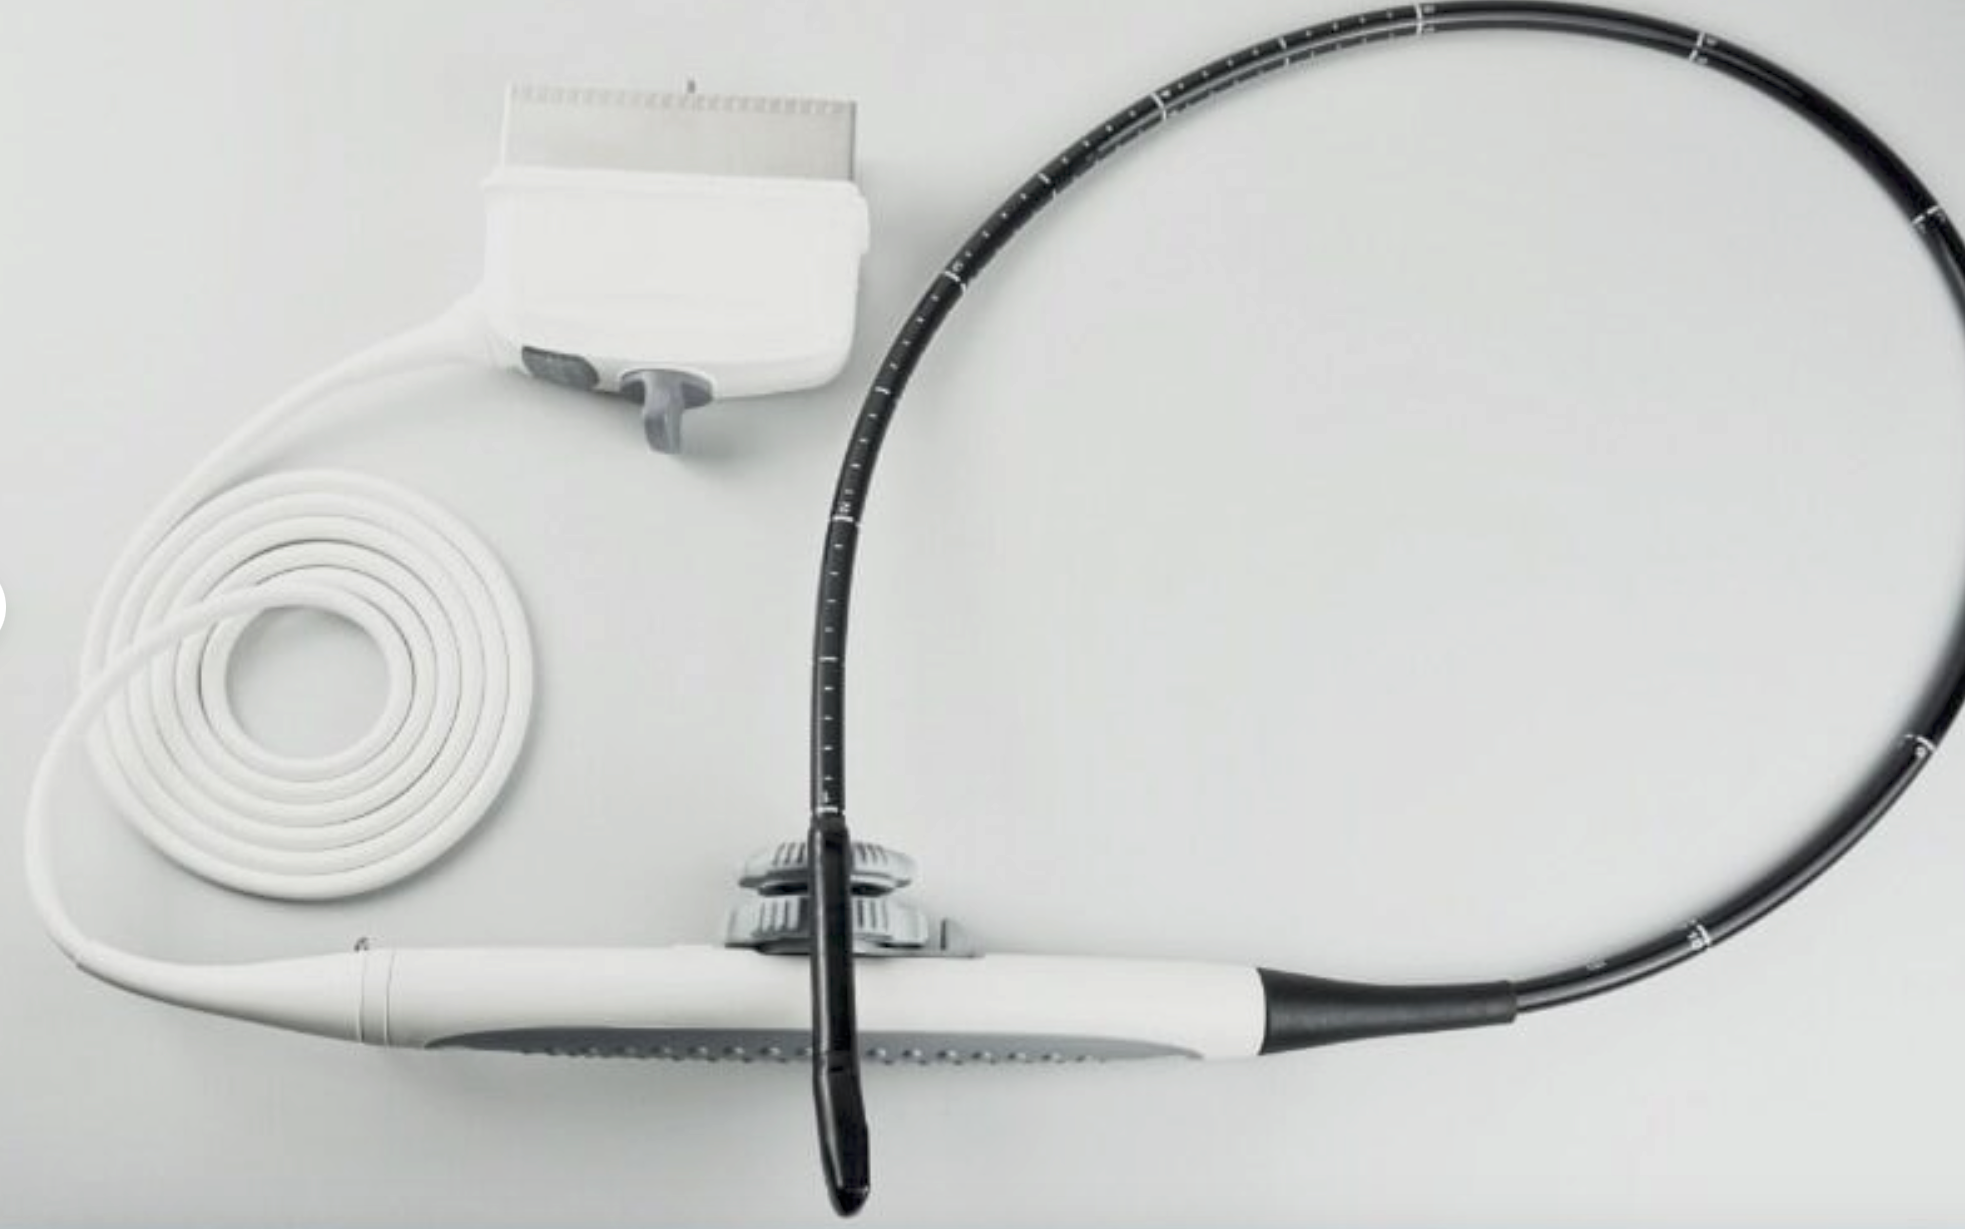

Sonde linéaire rectale |